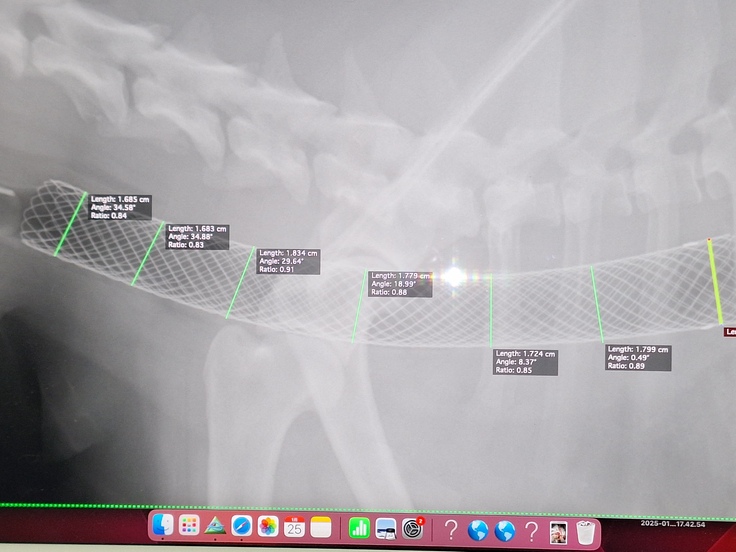

ステント挿入後のレントゲン

を添付させて頂きたいと思います。

クリニック様の許可を、頂いております。